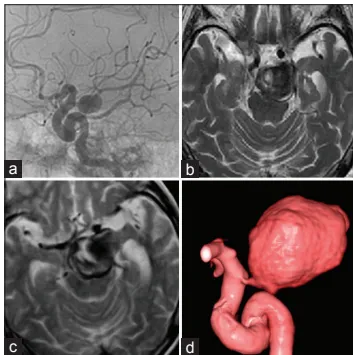

经过两年随访期,动脉瘤呈现快速生长趋势,尺寸从初始12mm增大至30mm,瘤体内形成血栓成分。增大的瘤体对脑干和丘脑区域产生压迫效应,患者出现右侧肢体无力、行走不稳、左眼睑下垂、眼球活动受限及吞咽困难等神经功能缺损症状。

影像学检查显示动脉瘤继续增大至35mm,接近标准乒乓球尺寸(40mm),瘤体表面出现薄弱区域("瘤泡"征象)。患者格拉斯哥昏迷评分降至11分(正常值15分),右侧肢体肌力评估为3级,改良Rankin量表评分达5分,呈完全依赖状态。

术前3D-CTA评估发现关键解剖特征:瘤体未见重要穿支血管发出,推测血栓形成已封闭血管开口,大脑后动脉可能建立代偿供血通路。基于此发现,手术团队决定实施动脉瘤夹闭孤立术联合血栓切除术。